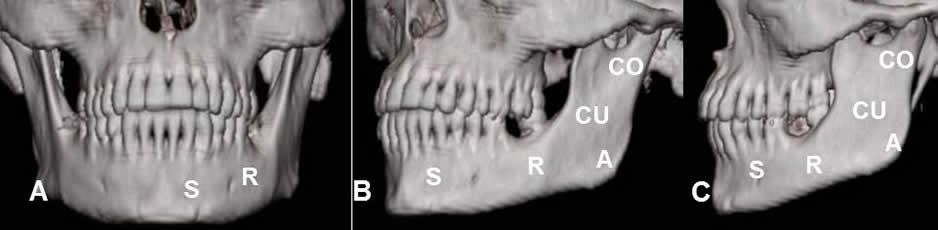

Fig 7. Mandíbula normal.

A, B y C: TAC reconstrucción 3D. Mandíbula normal, compuesta por el cóndilo (CO), el cuerpo (CU), el ángulo (A), el ramo (R) y la sínfisis (S).